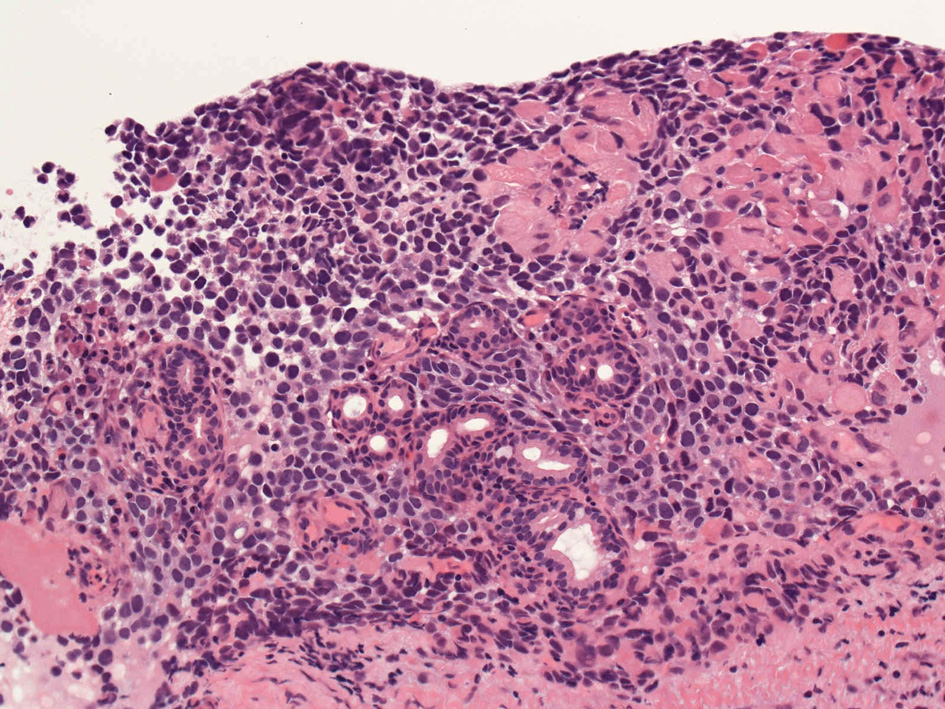

40歳女性 鼻粘膜腫瘤

右頸部のしこりを自覚。近医MRIで頸部多発リンパ節腫大あり当院を紹介される。右顎下, 右鎖骨上窩にも多数のリンパ節を触れる。穿刺細胞診ではcarcinoma疑い。右鼻腔, 上顎洞にも腫瘤が認められリンパ節腫大との関係を調べるために鼻腔腫瘤の生検が行われる。

病理組織所見

HE06.jpg

small round cell tumorの中でrhabdomyosarcomaは腫瘍細胞に種々の抗原が陽性となるため診断を誤ることがあり注意が必要である*1